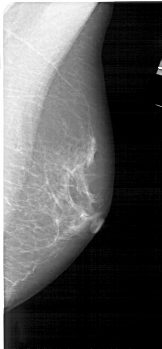

A_1545_1.LEFT_CC

LEFT_CC LINES 4876 PIXELS_PER_LINE 2206 BITS_PER_PIXEL 12 RESOLUTION 43.5 OVERLAY